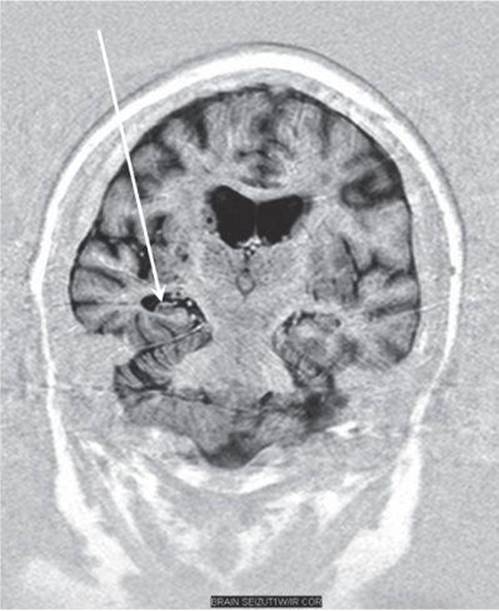

85. A 29-year-old man with a history of febrile seizures as a child has developed medication-refractory complex partial seizures within the past 2 years. An MRI reveals the abnormality indicated by the arrow. Which of the following is true regarding this condition?

85. The answer is a. (Ropper, pp 310-313.) The history and MRI are typical for MTS. The arrow in the MRI is specifically pointing at the sclerotic right hippocampus. This is the most common cause of intractable complex partial seizures in adults. The prognosis for improved seizure control with additional medications is poor; however, surgical resection of the right anterior temporal lobe may produce seizure freedom in up to 80% of cases. If this patient had a high-grade malignant brain tumor, he would probably die within 2 years. A cerebral angiogram may confirm the diagnosis of a vascular malformation.